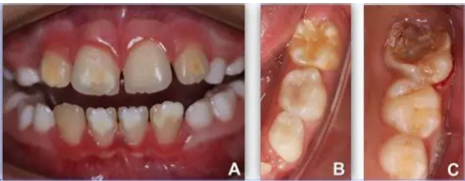

Dhëmbët shfaqin njolla që variojnë nga e bardha në të verdhë-kafe. Sa më të mëdha dhe më të

errëta të jenë zonat e çngjyrosura, aq më i rëndë është çrregullimi i mineralizimit. Mund të

preken vetëm pjesë të caktuara të dhëmbit ose e gjithë kurora. Dhëmbët me çngjyrosje të verdhë-

kafe kanë prirje më të lartë për t’u thërrmuar, pavarësisht higjienës orale. Nga kjo tendencë,

sëmundja mori emrin “dhëmbë si prej shkumësi”. Gjendja mund të përkeqësohet kur dhëmbët

bëhen tepër të ndjeshëm ndaj temperaturave (të nxehtit/ftohtit) ose thërrmohen plotësisht, duke

shkaktuar shqetësim të madh te fëmijët dhe prindërit.